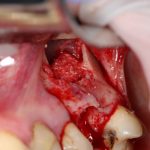

Кстати, обрати внимание на ширину альвеолярного гребня (левая картинка). Она чуть меньше 3 мм. Это объясняет, почему я засомневался в возможности установки имплантатов одновременно с остеопластикой. Понятно и без КЛКТ.

Наперво, мне нужно удалить разрушенный зуб и получить костный аутотрансплантат.